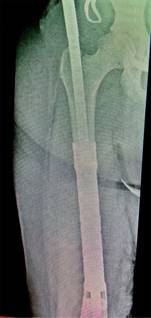

Con la paciente bajo anestesia general y en decúbito supino, se realiza asepsia, antisepsia y colocación de campos quirúrgicos estériles. Se opta por un abordaje anteromedial de fémur, mediante incisión longitudinal de aproximadamente 25 cm, disecando por planos hasta encontrar intervalo entre músculos recto femoral y vasto medial; después se encuentra el vasto intermedio, el cual se diseca hasta encontrar diáfisis femoral. Se observa tumoración en tercio medio de diáfisis femoral de aproximadamente 13 cm de longitud por 3 cm de ancho, el cual se reseca con bordes amplios, realizando osteotomía a 16 cm proximales de superficie articular de la rodilla (Figura 3); se envía muestra medular transquirúrgica, recibiendo confirmación de presencia de bordes libres por el Servicio de Patología. Se realiza segunda osteotomía a 16 cm distales del trocánter mayor, se envía segunda muestra de médula ósea, recibiendo reporte negativo para células malignas. Se realiza rimado de fémur proximal y distal con rimas diámetros 9, 10 y 10.5 hasta atravesar fosa digital proximalmente; se coloca asentador para hueso, regularizando el límite de la osteotomía. Se introduce clavo endomedular hasta limite distal establecido (Figuras 4 y 5) y se coloca prótesis diafisaria (Figura 6) con asentadores y coronas en extremos diafisarios, respectivamente. Se procede a colocar pernos de bloqueo, verificándose longitud de extremidad (Figura 7) comparando con la contralateral. Se repara intervalo entre recto femoral y vasto medial y se procede a cierre por planos.